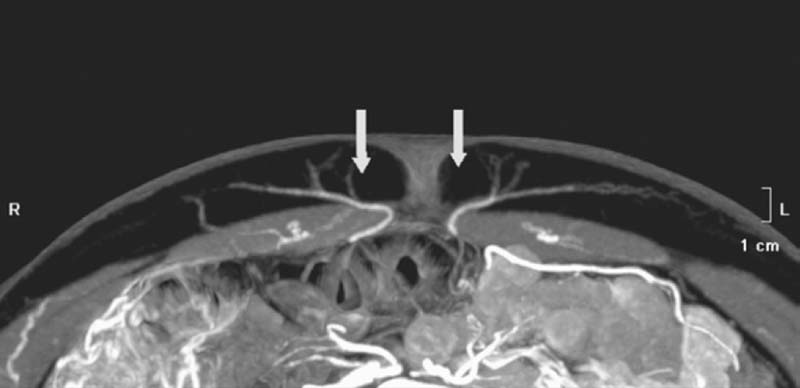

Detailed knowledge of the deep inferior epigastric vasculature and its perforator topography is required for successful execution of the DIEP flap. Accurate knowledge of the perforator topography may be obtained via preoperative imaging—either CTA or MRA. The largest perforator vessels may be chosen preoperatively and then mapped on an X-Y axis. A large perforator trumps the location. Prior to the era of preoperative imaging, the flap was based on one perforator 20% of the time and usually used the lateral row.8 With preoperative imaging, one perforator flap is used 70% of the time, and the medial row is used in 75% of cases. In 8% of patients, a septocutaneous or paramuscular perforator may be found in which the dominant perforator vessel travels around the medial edge of the rectus abdominis muscle with no intramuscular course at all ( Fig. 4.1 ). This completely eliminates any intramuscular dissection and damage to the musculature, and the best way to identify a septocutaneous perforator is via preoperative imaging ( Fig. 4.2 ). Often, the best perforator vessels are around the umbilicus or slightly above the umbilicus. In these situations, The DIEP flap is designed to incorporate the largest and most robust perforator vessels as seen on preoperative imaging.

Increasing numbers of microsurgeons who routinely perform perforator flap breast reconstruction identify the main perforators of the deep inferior epigastric vasculature preoperatively via CTA or MRA. This enables them to obtain precise information on perforator diameter and three-dimensional course. A handheld Doppler probe is used to confirm the vessels that they choose preoperatively, and then identify them with direct visualization during flap harvest and perforator isolation.